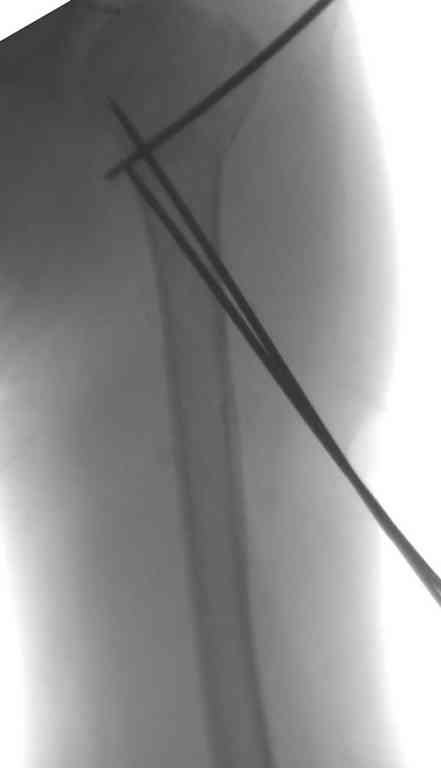

Неправильно выбранная тактика по фиксации или технические ошибки во время операции могут привести к серьезным осложнениям. Здесь привожу

пример из нашей практики, вроде обычный перелом шейки, фиксированный популярным методом "Сиэтла" - множественными спицами 2.8 мм с резьбой на конце.

При первичном осмотре в поликлинике через 3 недели обнаружили миграцию двух спиц, срочно госпитализированному на второй день перед операцией на всякий случай сделали снимок, одна спица находилась под ключицей в шейном отделе (на снимке).

Сделали напряженными спицами по методике А.Ф.Лазарева со товарищи Репозиция сделана спицевым дистрактором, проксимальная спица была проведена в полскости деформации перпендикулярно оси наклонившейся головки. Получилось все довольно легко. Спицы малость покороче можно было сделать, ну да удалять потом легче будет.

Картинка в приложении.